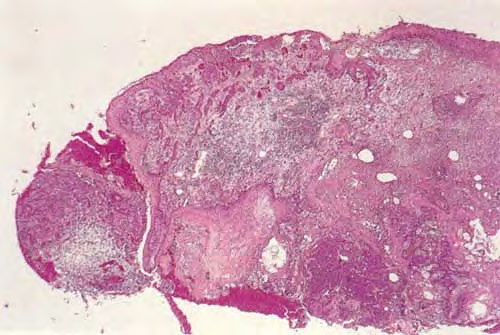

Sebaceous carcinoma = الكارسينوما الدهنية